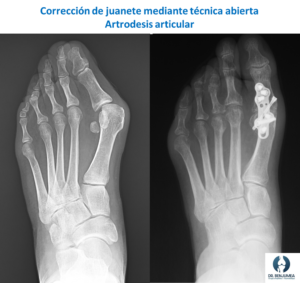

Existen múltiples técnicas correctoras de la deformidad. A nivel general encontramos dos tipos de procedimientos, aquellos que consisten en cirugía abierta y otros que se realizan de forma percutánea (cirugía láser del pie). Cada técnica aporta unas ventajas y unas desventajas. Lo ideal es ofrecer a cada paciente la técnica que más le convenga en cada caso.

- Cirugía abierta: Dentro de la cirugía abierta existen muchísimas técnicas que pueden emplearse. La ventaja principal es que la corrección anatómica y radiográfica suele ser superior a la otra técnica, logrando una corrección exacta. La principal desventaja es que, al ser una técnica abierta, aumenta el daño a la piel y el tejido blando, aumentando el riesgo de infección, de problemas con la piel y la rigidez postoperatoria.